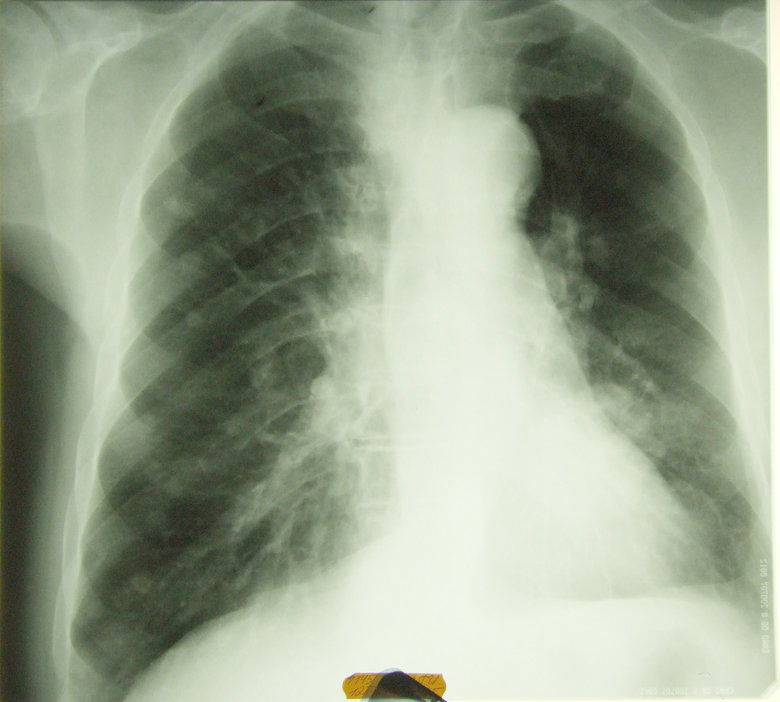

Периферический рак

Обсуждалось здесь viewtopic.php?f=24&t=867